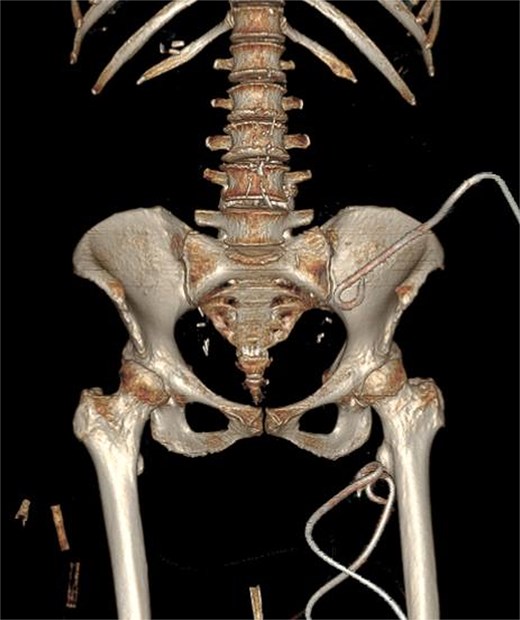

Due to the complex anatomy, a single access was deemed insufficient. Under real-time ultrasound and fluoroscopic guidance, a retroperitoneal approach was first used: an 18-G needle and guidewire were advanced in the left midaxillary line parallel to the iliac crest, followed by tract dilation and placement of a 12-G pigtail catheter into the psoas component. Subsequently, two additional 12G catheters were placed percutaneously via a femoral approach into the thigh extension (Fig. 2). In total, ~200 ml of purulent material was drained. The localization of the drains was confirmed by subsequent CT (Fig. 3).

Ultrasound and fluoroscopy show multi-access percutaneous drainage with one retroperitoneal and two femoral catheters. (A) Ultrasound-guided retroperitoneal puncture into the psoas collection. (B) Fluoroscopic image demonstrating catheter placement in the psoas component. (C) Ultrasound-guided puncture of the thigh extension. (D) Fluoroscopic confirmation of one retroperitoneal and two femoral drains in situ.